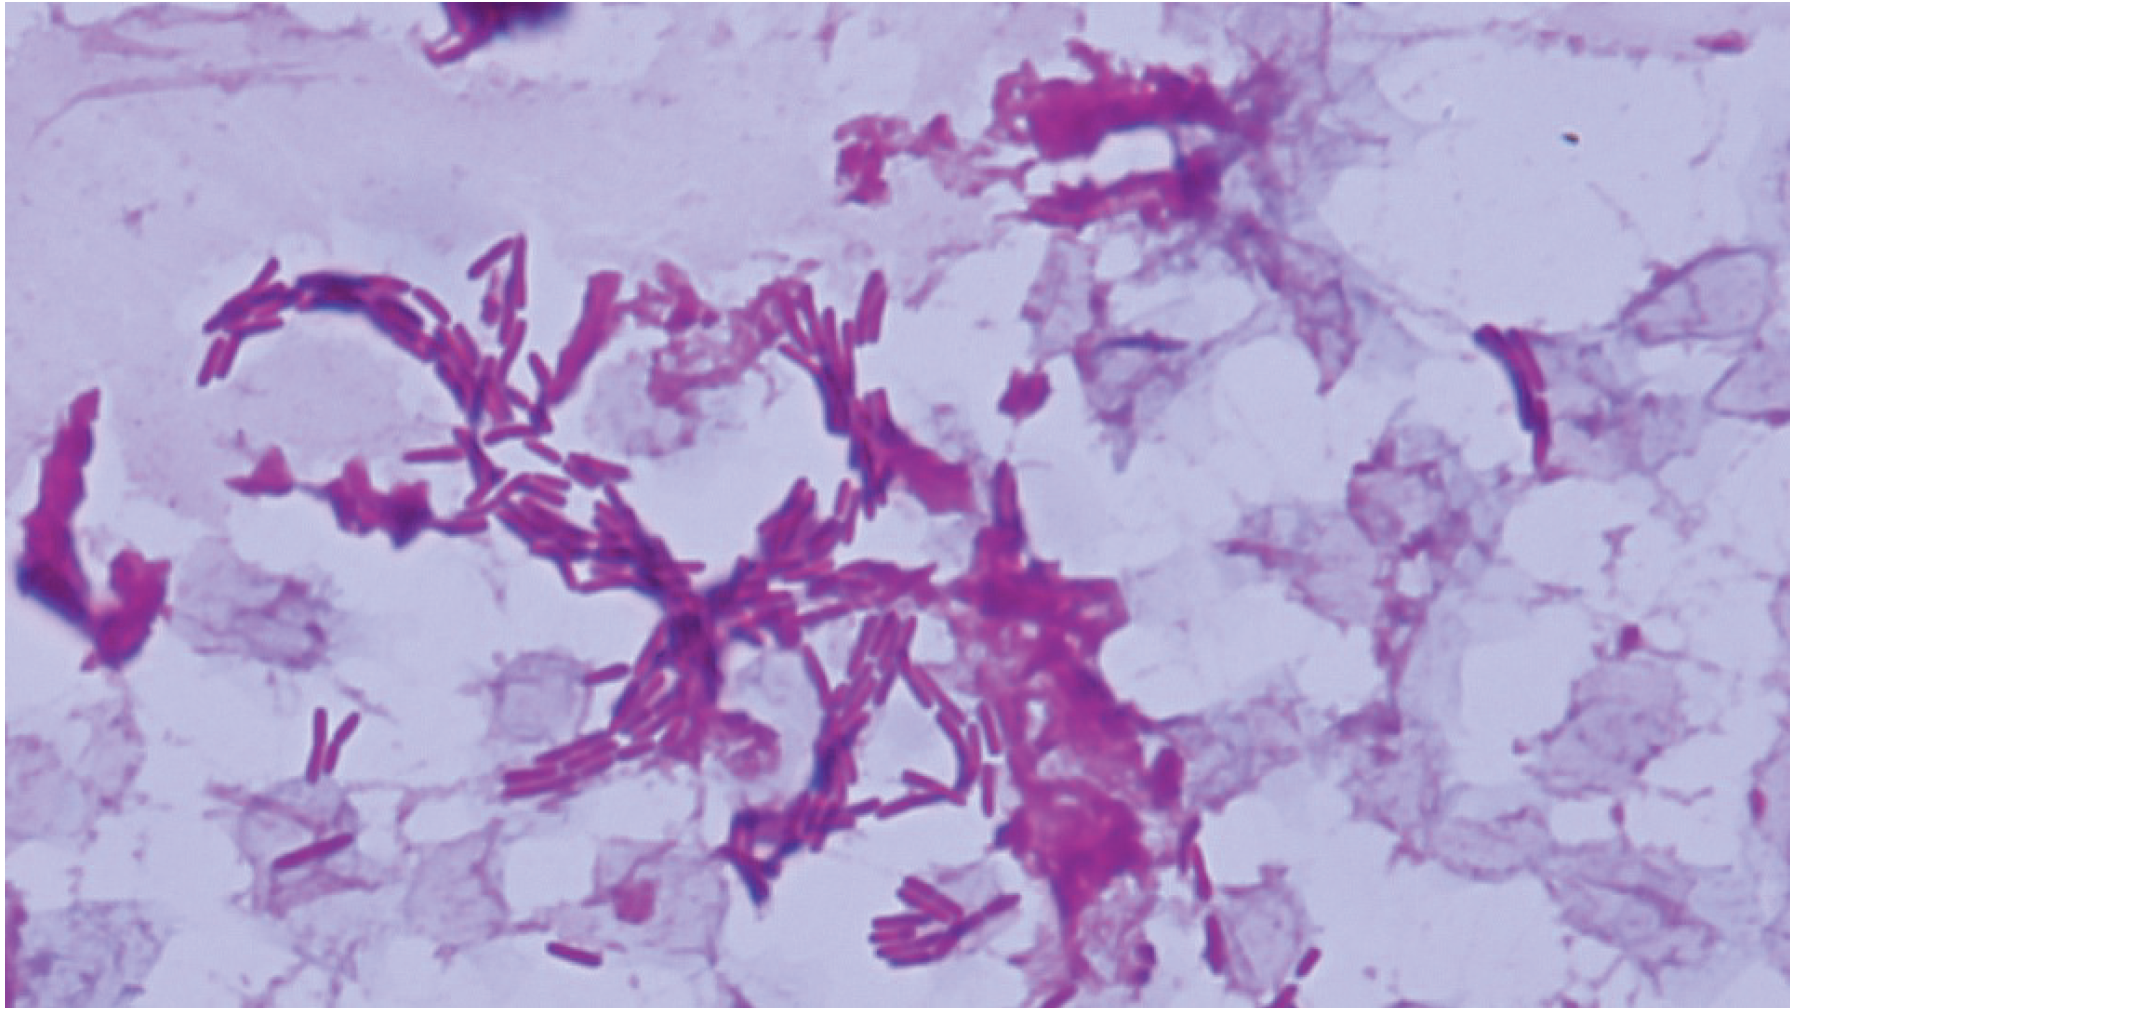

血液培養検査で培養陽性になった好気ボトル内容液のGram染色標本を示す。嫌気ボトルは培養陰性であった。分離菌はオキシダーゼテスト陽性であった。

推定されるのはどれか。

Acinetobacter baumannii

Escherichia coli

Haemophilus influenzae

Klebsiella pneumoniae

Pseudomonas aeruginosa